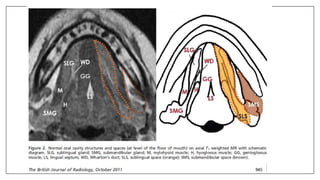

MR Sialography

• MR-Si is a noninvasive method of imaging the ductal system of

submandibular gland and parotid gland.

• This MR technique has the potential to provide a comprehensive

examination for the detailed anatomic assessment of the major salivary

glands.

• The patient’s salivary secretion is used as contrast agent, method of

examination based on a basic principle of usingT2-weighted sequence for

monitoring liquids.

• Its superior properties also include its capability of displaying the duct

diameter in its actual value due to the nonuse of the contrast agent.